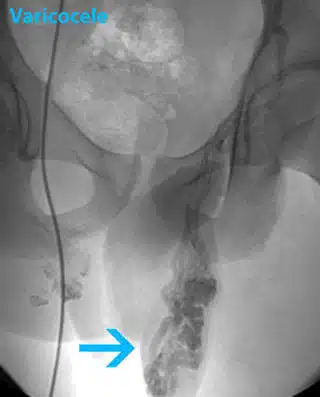

3. استئصال الدوالي بطريقة الانصمام عن طريق الجلد

يتم إجراء هذا العيادة الخارجية تحت التخدير الموضعي. تعتبر هذه الطريقة الأقل بضعاً في جراحة الدوالي. يقوم الطبيب بإدخال قسطرة في وريد من خلال الفخذ. يمرر القسطرة من خلال الأنبوب ويرى الأوردة المتضخمة على الشاشة بواسطة كاميرا متصلة بالقسطرة. يقوم بإطلاق لفائف أو محلول يجعل الندوب لخلق انسداد في أوردة الخصية و إصلاح دوالي الخصية. من مزايا استئصال الدوالي بطريقة الانصمام عن طريق الجلد بأنها غير باضعة نسبياً، بالإضافة إلى أهميتها في الحفاظ على الشريان الخصوي.